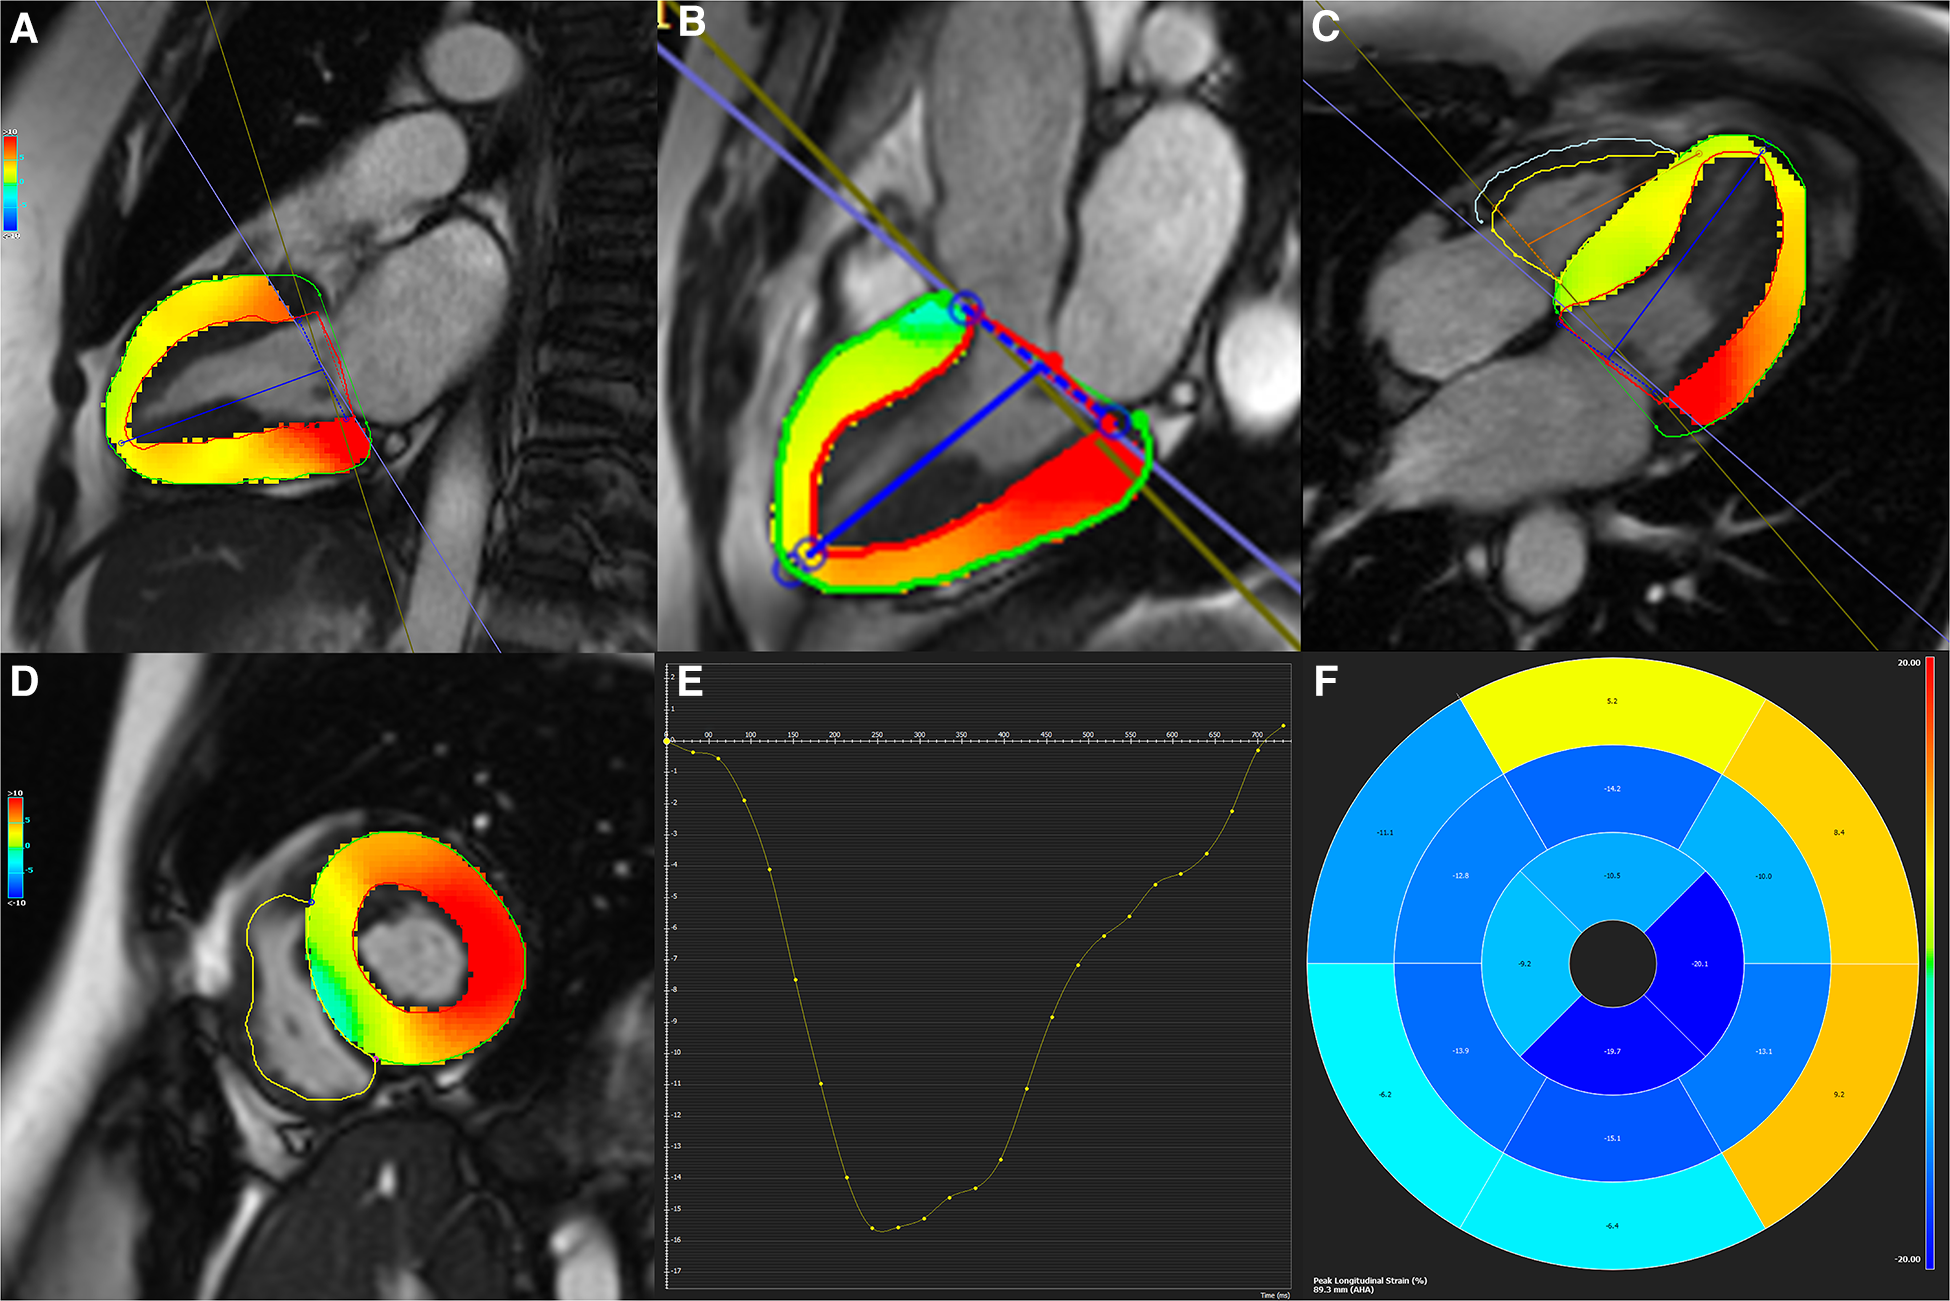

LV end-diastolic and end-systolic frames of 2-, 3- and 4-chamber views and the short-axis plane were selected. Optimal brightness adjustment was done to ensure the best contrast to make accurate discrimination between the endocardium and the blood pool. The endocardial and epicardial contours were defined manually and propagated throughout the slices, and 3D LV strains, consisting of global longitudinal (GLS), global circumferential (GCS), and global radial (GRS) strains, were calculated utilizing the CMR-FT method (Figure 2). The absolute values of strains were utilized for analysis.

Figure 2

(A–D) Two-, three-, and four-chamber as well as short-axis cine functional sequences with defined endocardial and epicardial contours. (E) Strain curve, and (F) Bull's eye map are depicted for global circumferential and longitudinal strains.